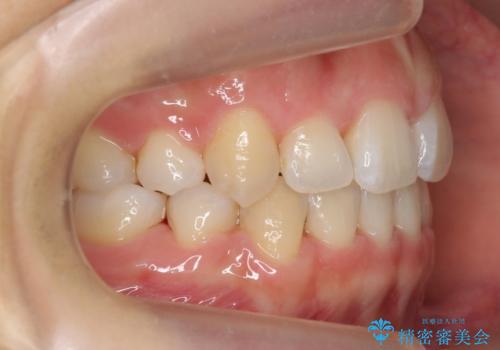

ワイヤー矯正は時間はかかりますが、仕上がった後の自然な美しさは他の追随を許しません。

歯を抜いたことで、口元が下がって、横顔も理想的なラインになりました。

美容整形よりも、自然な美しさを。口元は大事です。